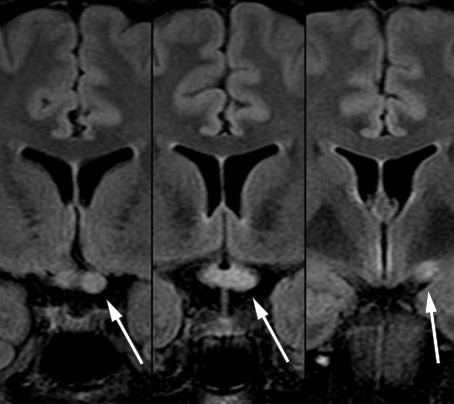

Etter utskrivelse viste det seg at den andre anti-MOG-prøven fra serum var positiv. Mot slutten av nedtrappingen av prednisolon hadde pasienten to korte innleggelser i medisinsk avdeling på grunn av vedvarende hodepine og urinveisinfeksjon. MR av hjerne og ryggmarg og nevrologiske undersøkelser viste da ikke noe nytt. Rett etter avsluttet prednisolonkur ble pasienten innlagt på nevrologisk avdeling med økende synsproblemer, diplopi, nystagmus mot høyre og parese for abduksjon av høyre øye. MR 20 dager etter forrige undersøkelse og nesten to måneder etter oppstart med rituksimab viste tilkomne lesjoner subkortikalt frontalt bilateralt, i medulla, i venstre lillehjernepedunkel samt i corpus callosum (figur 4). Lumbalpunksjon viste fortsatt moderat pleocytose (tabell 1, siste kolonne). Pasienten fikk som tidligere metylprednisolon med god effekt, og ble deretter skrevet ut til hjemmet med langvarig nedtrapping av prednisolon og snarlig kontroll på poliklinikken.

En tredje prøve bekreftet at anti-MOG var positiv. Pasientens samlede sykehistorie, inkludert forverringer kort tid etter avslutning av prednisolon, er også vel forenlig med anti-MOG-encefalomyelitt (7). Lesjoner i corpus callosum er vanlig ved multippel sklerose, men forekommer også ved anti-MOG-encefalomyelitt hos voksne (8).